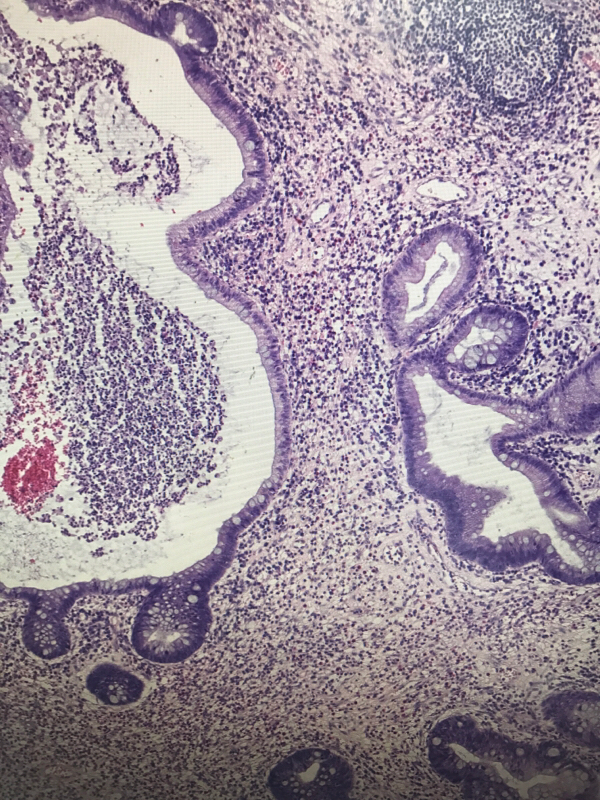

直肠息肉

性别

男

年龄

19

临床诊断

一般病史

血便4天

标本名称

大体所见

灰红结节一枚,大小1✖️0.6✖️0.6cm,切面灰红,质软

管状腺瘤,低级别还是高级别?

幼年性息肉,灶性低级别

考虑有高级别

幼年性息肉?

幼年性息肉